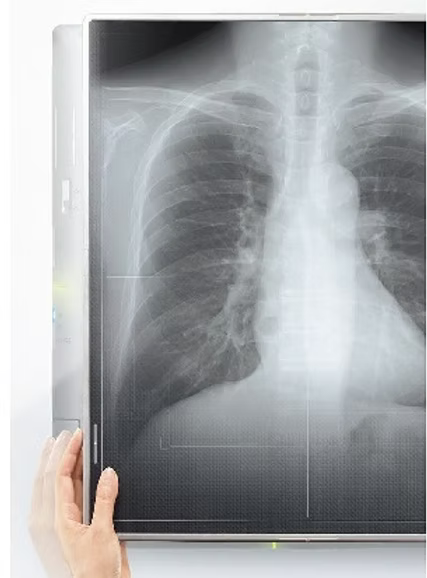

フラットパネルエックス線撮影システムの紹介

当院では、富士フイルムメディカル製の最新フラットパネルエックス線撮影システム(FPD:Flat Panel Detector)を導入し、従来のフィルム式レントゲン撮影を大幅に上回る高画質・低被曝のデジタルX線検査を提供しております。富士フイルムの先進的な画像処理技術により、より正確で迅速な診断を実現しています。

フラットパネル撮影システムの特徴とメリット

圧倒的な高画質

従来のフィルム撮影と比較して、約10倍の情報量を持つデジタル画像により、微細な病変や早期の変化も鮮明に描出できます。富士フイルム独自の画像処理技術「ISS(Intelligent Smart Sensor)」により、最適な画質で撮影されます。

大幅な被曝線量削減

フラットパネルの高い感度により、従来システムと比較して約30-50%の被曝線量削減を実現。患者様により安全な検査環境を提供いたします。

瞬時の画像確認

撮影後数秒で高精細なデジタル画像が表示され、再撮影の必要性を即座に判断できます。検査時間の短縮と患者様の負担軽減につながります。

バーチャルグリッド Virtual Grid